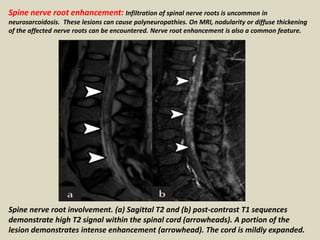

Spine nerve root enhancement: Infiltration of spinal nerve roots is uncommon in

neurosarcoidosis. These lesions can cause polyneuropathies. On MRI, nodularity or diffuse thickening

of the affected nerve roots can be encountered. Nerve root enhancement is also a common feature.

Spine nerve root involvement. (a) Sagittal T2 and (b) post-contrast T1 sequences

demonstrate high T2 signal within the spinal cord (arrowheads). A portion of the

lesion demonstrates intense enhancement (arrowhead). The cord is mildly expanded.